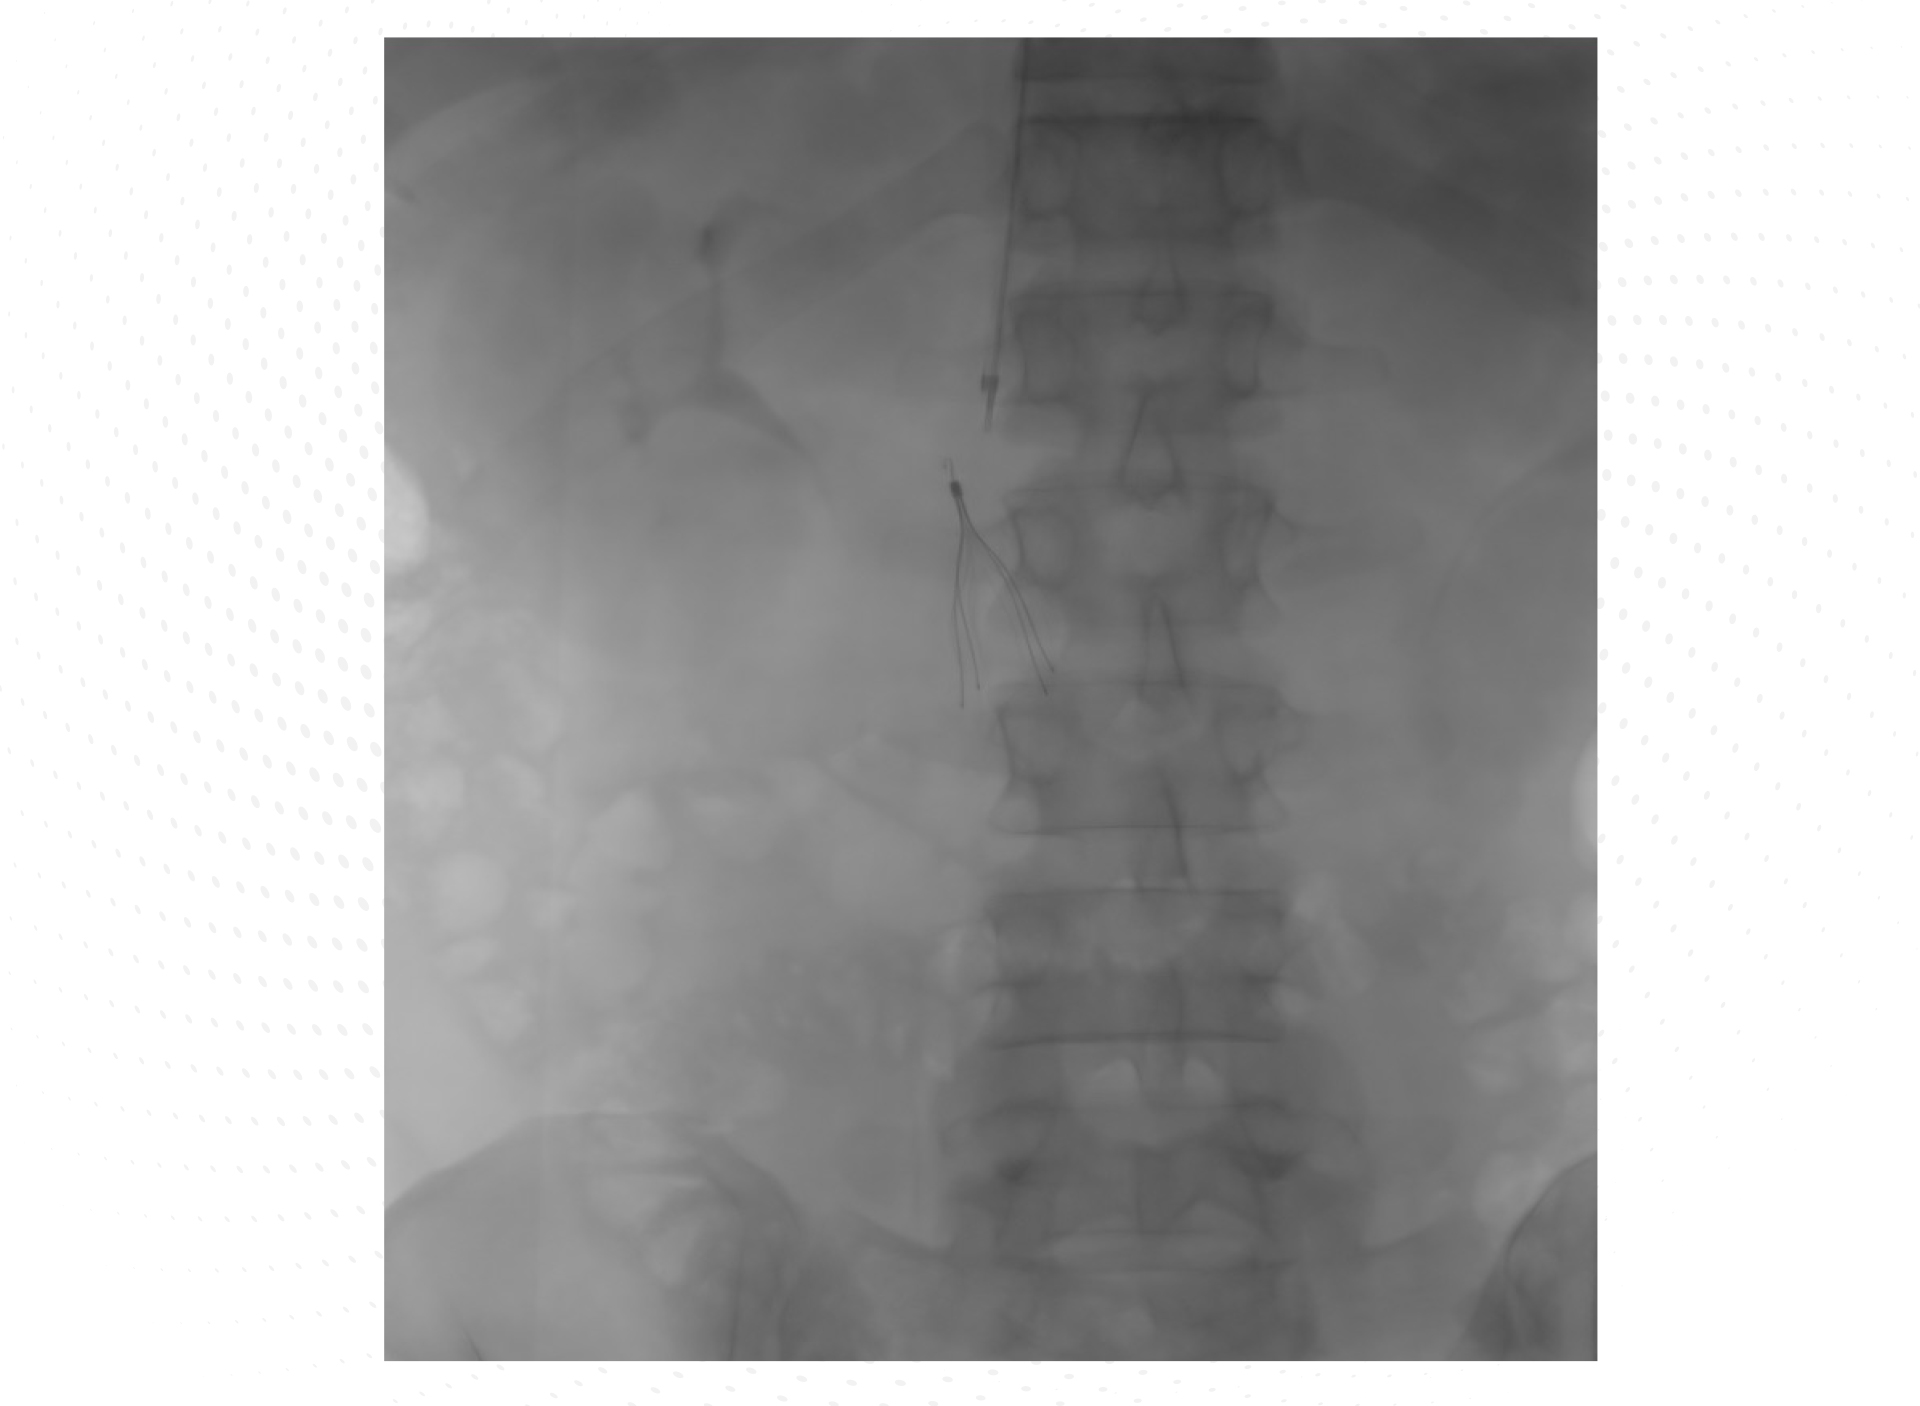

• El paciente se da de alta, manteniendo el tratamiento anticoagulante con apixabán 5 mg/12 h por vía oral (v.o.) y se programa la extracción del FVC, que finalmente no fue posible por progresión del trombo de la vena cava a nivel caudal al filtro, con extensión a ambas venas iliacas (Figura 1).